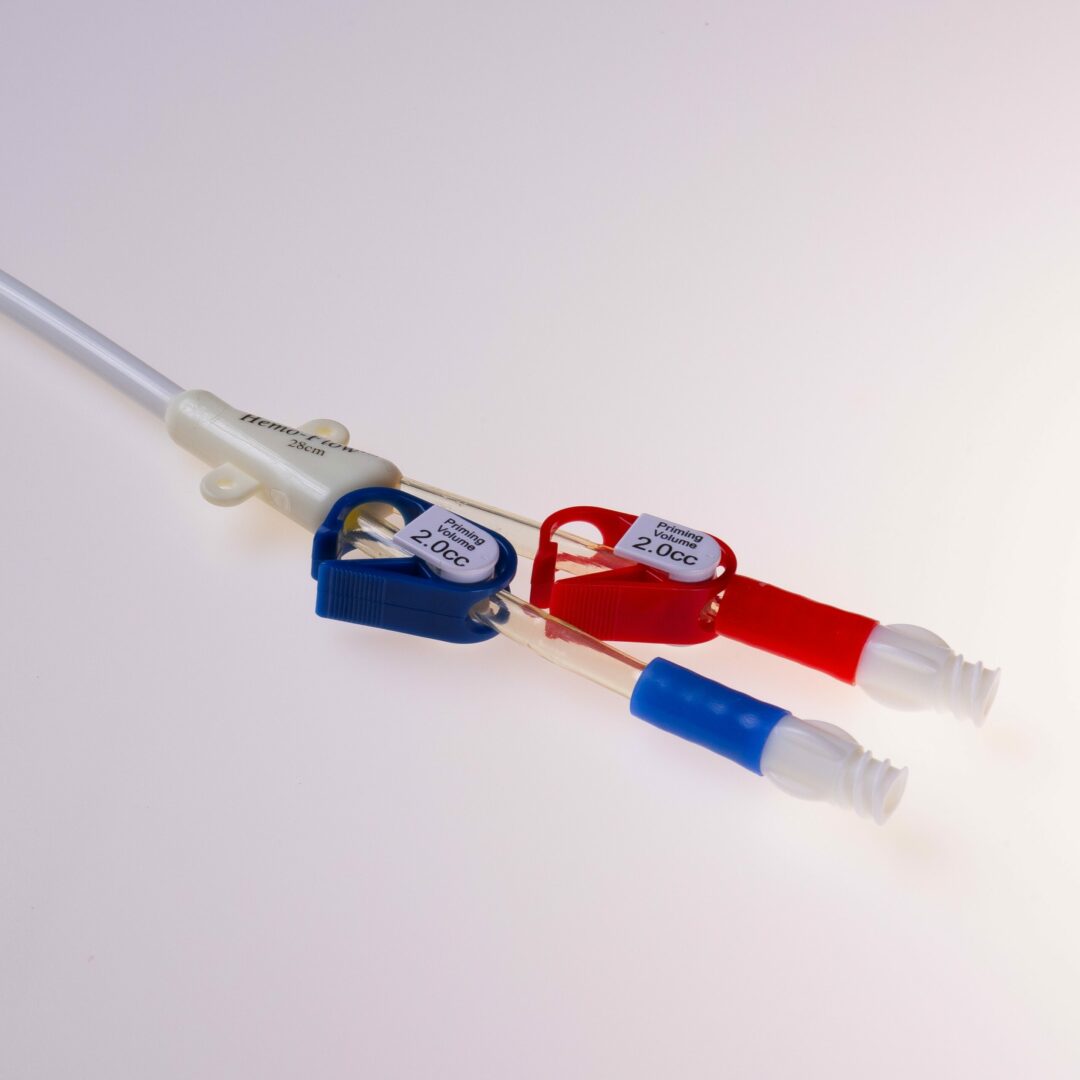

Der HFS Hemo Flow® ist ein untertunnelter Langzeitdialysekatheter für die chronische Hämodialyse. Er ermöglicht einen mehrjährigen, verlässlichen Gefäßzugang im Dialysebetrieb.

Der HFS Hemo Flow® ist ein untertunnelter Vorhofkatheter für die chronische Hämodialyse.

Der HFS Hemo Flow® wird antegrad untertunnelt. Die Einführung in das Gefäß erfolgt über eine Splitkanüle mit Schleuse.